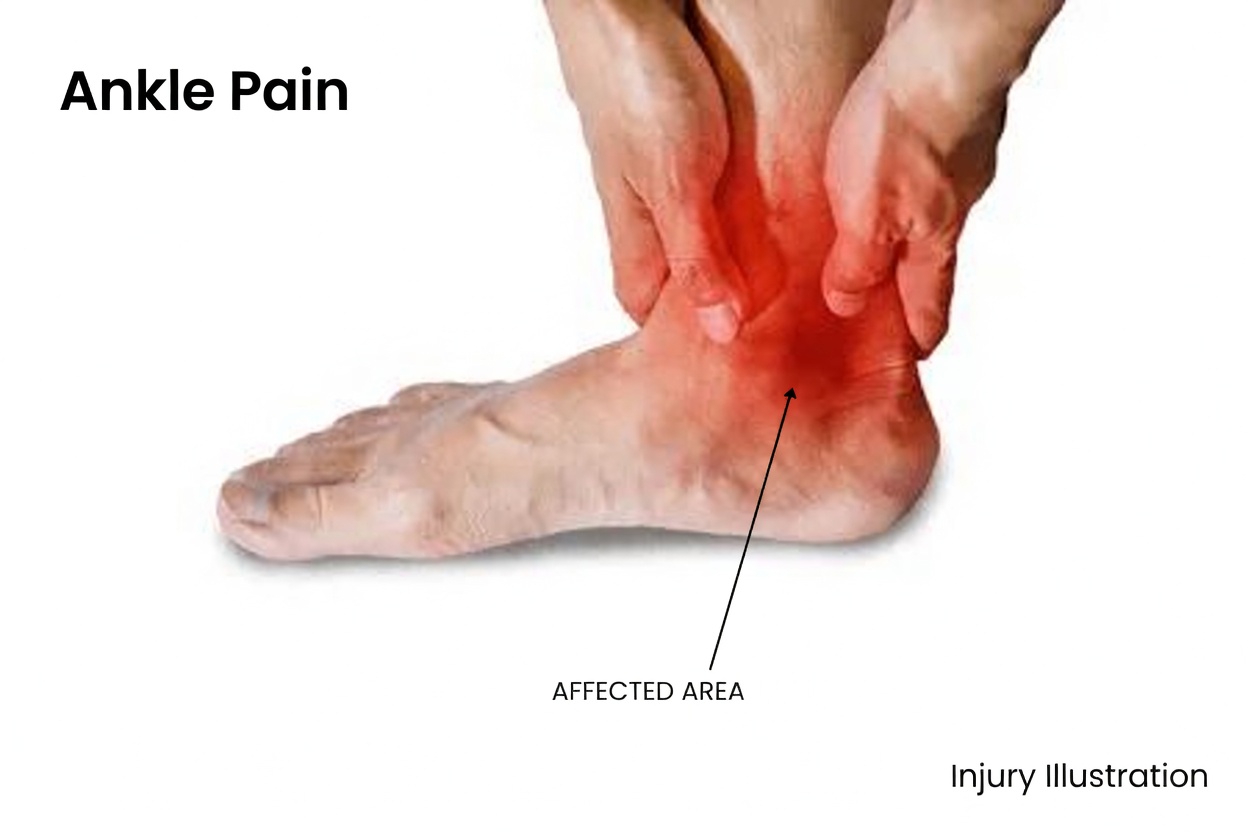

- Swelling in the ankles or feet

Ankle and foot swelling, also called edema, is one of the most common side effects of amlodipine. Because the medication relaxes blood vessels, fluid can build up in the lower legs. Many people notice this more in the evening after being on their feet for much of the day.

Not everyone will experience these reactions, and many side effects become less noticeable as the body adjusts. Even so, they can interfere with routine activities. Swelling may make shoes feel tight, while dizziness may cause you to slow down during a walk or hesitate before standing up.

Is ankle swelling from amlodipine serious?

Ankle swelling is one of the most common side effects and is usually not dangerous. However, if the swelling appears suddenly, is painful, or only affects one leg, you should inform your doctor.